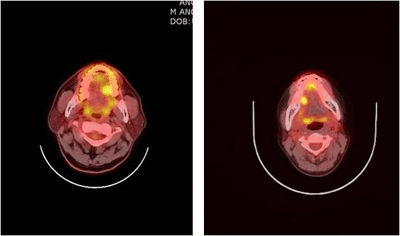

양전자방출단층 촬영(Positron Emission Tomography, PET)

양전자방출단층촬영(PET)는 각 장기의 생화학적, 생리적 반응을 정량화하여 진단, 치료방침설정 등에 활용하는 영상기법으로 양전자의 방출 후 나타나는 광자를 검출기를 통해 검출하는 것을 기본원리로 합니다. 구강점막 등에 발생한 악성흑색종에 대한 병기 결정에도 도움이 되는 것으로 알려져 있습니다.

좌측, 우측 설암의 양전자방출단층 촬영 이미지

[좌측, 우측 설암의 양전자방출단층 촬영 이미지]